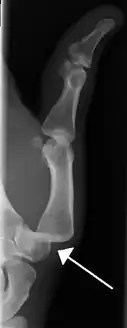

![]() | |

| A traumatic dislocation of the tibiotarsal joint of the ankle with distal fibular fracture. Open arrow marks the tibia and the closed arrow marks the talus. | |